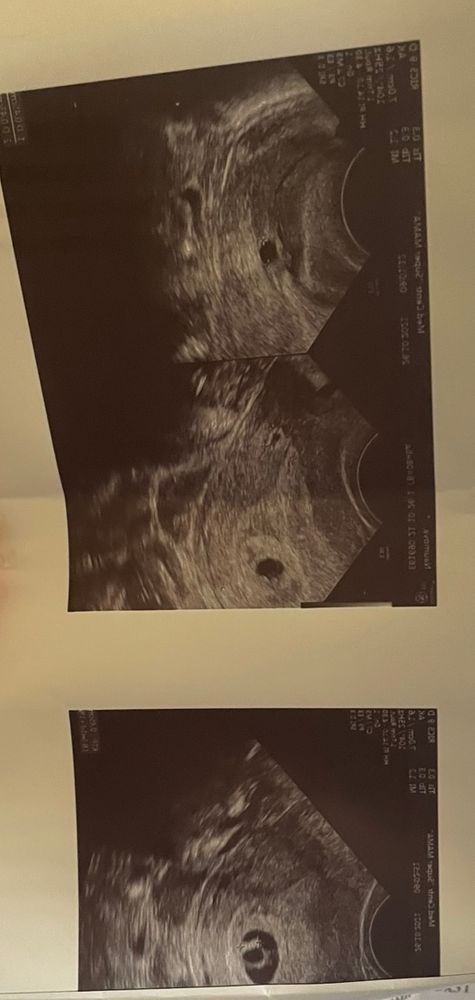

Mari, я ещё раз посмотрела Ваше узи. Да там желточный мешок великоват, обычно он на этом сроке около 4 мм. У меня по нему врач предположил ЗБ, и он за два дня очень увеличился. У Вас бы сравнить его с первым узи. И часто когда увеличен желточный мешок, проблема ЗБ кроется именно в генетике эмбриона. У меня так и получилось, был сбой в генетике эмбриона.

Я бы на вашем месте прислушалась к своим ощущениям, у меня есть опыт неправильно диагностировали беременность, в три голоса врачи говорили замерла. А у меня все признаки беременности продолжались. Ждала я дней 10, вставляла утрожестан 200 утром и 200 вечером, выделения прекратились, потом записалась к лучшему узисту в городе к Пробочай на Гоголя. И о чудо, эмриончик то оказался очень даже живой и жизнеспособный, просто не каждый аппарат видит отчётливо сердцебиение. И малыш соотвецтвывал на то время сроку. А стоило всего то подождать. Да была паника, огорчение и страх. Ведь перед этим действительно была у меня замерла, но я сразу нашла причину, у меня подскочил гормон ТТГ и я понимала что контур плотного яйца на снимке не чёткий и размытый, а у вас на снимке, он чёткий. Я не врач но нужно прислушаться к своему сердцу и наверное немного подождать. Ведь если все то дней через 10 ничего не изменится и даже с поддержкой утрожестана плодное яйцо будет кровать и выйдет.